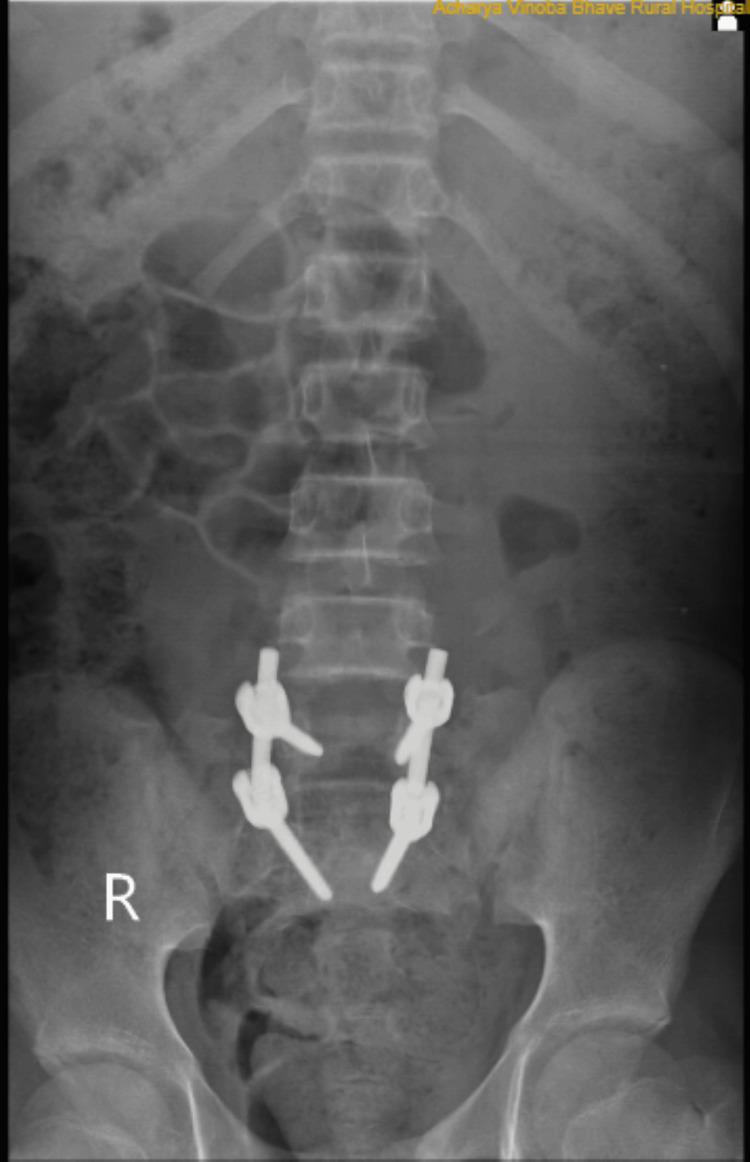

More than 100% of the traumatic subluxation of one vertebral body over another in the coronal or sagittal plane is known as traumatic spondyloptosis, which typically results in the contusion of the spinal cord. It is an uncommon yet severe spinal column injury. Here, we present traumatic lumbosacral spondyloptosis at the L5 and S1 levels with complete spinal cord compression with paraplegia and bowel and bladder involvement. The patient underwent posterior spinal fusion (delta fixation) and decompression. The patient improved his motor and sensory deficits at one-month follow-up. By the eighth-month follow-up, the patient had recovered entirely from his motor and sensory deficits and was stable for the entire year.

一个椎体在冠状面或矢状面上相对于另一个椎体超过100%的创伤性半脱位被称为创伤性椎体滑脱,这通常会导致脊髓挫伤。它是一种罕见但严重的脊柱损伤。在此,我们报告一例L5和S1水平的创伤性腰骶椎体滑脱,伴有完全性脊髓受压、截瘫以及肠道和膀胱受累。患者接受了后路脊柱融合术(三角固定)和减压手术。在术后1个月的随访中,患者的运动和感觉功能缺损有所改善。到术后8个月随访时,患者的运动和感觉功能缺损已完全恢复,并且一整年情况稳定。